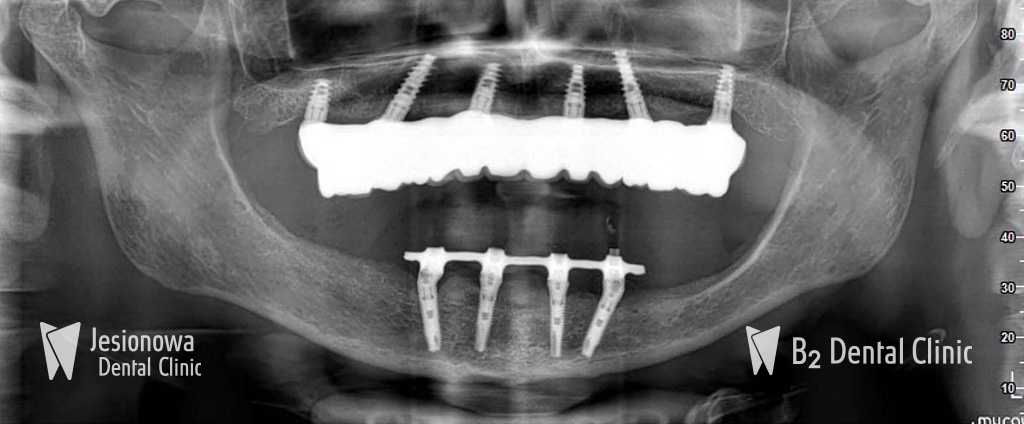

Double All on 4

All on 6 + All on 4

All on 4